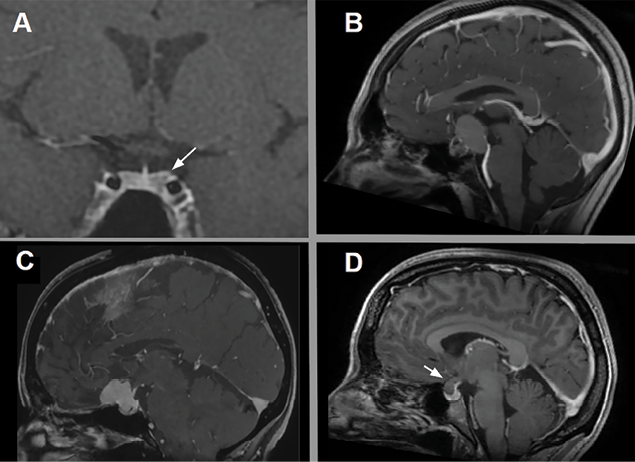

Las lesiones selares más frecuentes son los adenomas hipofisarios y representan alrededor del 90% (prolactinomas 57%, adenomas no funcionantes 28%, adenomas secretores de somatostatina 11% y adenomas secretores de ACTH 2%) (Fig 1 A)2.

Figura 1. Lesiones selares más frecuentes. A: Adenoma hipofisario. B: Craneofaringioma. C: Meningioma del tuberculum selar. D: Quiste de la bolsa de Rathke